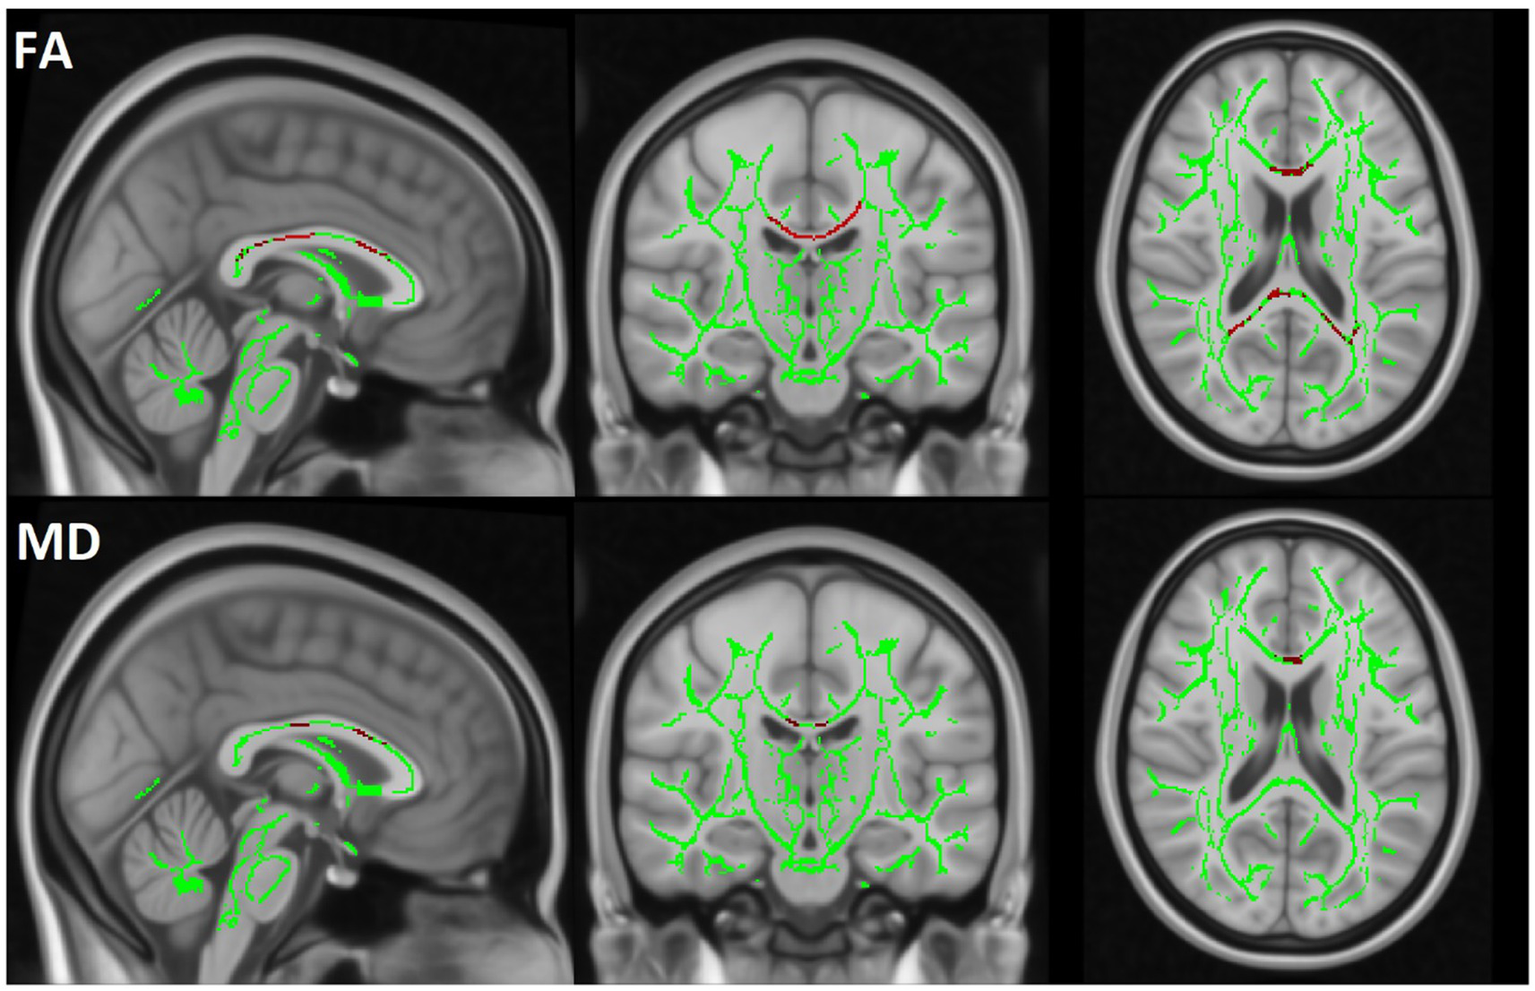

TBSS analysis revealed a significant decrease in FA and an increase in MD in the MBP group compared to the control group. Additionally, a significant decrease in FA and an increase in MD were observed when comparing the MBP group to the MBN group. The statistical results of the TBSS analysis are presented in Table 6. The significant results of the MBP-CON group comparison are shown in Figure 6 while the significant results of the MBP vs. MBN group comparison are displayed in Figure 7.

Figure 6

The TBSS results comparing the MBP and CON groups are displayed. The skeleton mask is overlaid in green on the MN152 template, while voxels exceeding the 0.95 threshold are highlighted in red along the skeleton. The first row represents FA and the second row MD results.

To ensure robust assessment of WM alterations, we applied multiple complementary analytic approaches, including region-based segmentation and voxel-wise statistics. Covariates such as age and sex were also accounted for, given their known influence on WM microstructure. The consistency of findings across different WM analysis approaches—particularly in the CC—highlights the robust relationship between MBs and disrupted WM integrity. Notably, the observed decrease in FA and increases in MD in MBP patients suggest widespread microstructural damage beyond MBs. Importantly, the observed alterations agree with a comprehensive systematic review by Wortzel et al., which synthesized results from 66 studies examining diffusion changes following acute and subacute TBI. Their analysis identified decreased FA alongside increased MD and RD as the most consistent diffusion alterations associated with TBI in adults (41). The direction and pattern of DTI parameter changes in our cohort align with this broader literature. The TBSS analysis further reinforced the relevance of MBs, as significant WM alterations were observed in the MBP group compared to CON group in FA and MD, whereas the MBN group showed no significant alteration. In the comparison between the MBP and MBN groups, FA was significantly reduced, while MD were increased, further supporting the presence of more severe injury in the MBP group.